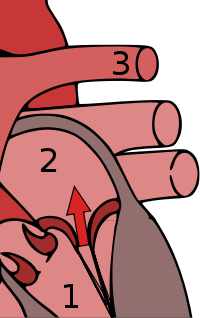

Mitral valve prolapse is frequently associated with mild mitral regurgitation,[7] where blood aberrantly flows from the left ventricle into the left atrium during systole. In the United States, MVP is the most common cause of severe, non-ischemic mitral regurgitation.[1] This is occasionally due to rupture of the chordae tendineae that support the mitral valve.[5]

The mitral valve, so named because of its resemblance to a bishop's mitre, is the heart valve that prevents the backflow of blood from the left ventricle into the left atrium of the heart. It is composed of two leaflets, one anterior and one posterior, that close when the left ventricle contracts.

Each leaflet is composed of three layers of tissue: the atrialis, fibrosa, and spongiosa. Patients with classic mitral valve prolapse have excess connective tissue that thickens the spongiosa and separates collagen bundles in the fibrosa. This is due to an excess of dermatan sulfate, a glycosaminoglycan. This weakens the leaflets and adjacent tissue, resulting in increased leaflet area and elongation of the chordae tendineae. Elongation of the chordae tendineae often causes rupture, commonly to the chordae attached to the posterior leaflet. Advanced lesions—also commonly involving the posterior leaflet—lead to leaflet folding, inversion, and displacement toward the left atrium.[12]